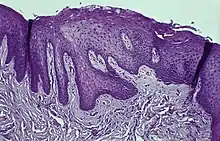

Histology

Immunohistochemical staining with FXIIIa [9] antibody disclosed a population of reactive spindle- or stellate-shaped cells[10] in 11 of 15 cases, located in connective tissue papillae and in a few cases also distributed throughout the lesion. The FXIIIa-stained cells appeared together with the frequently observed stellate, "young" occasionally multinucleated fibroblastic cells observed in more than 50% of patients aged 10–69 years. It is likely that FXIIIA-expressing "mucosal dendrocytes" are pathologically involved in some way.[11][12][13]